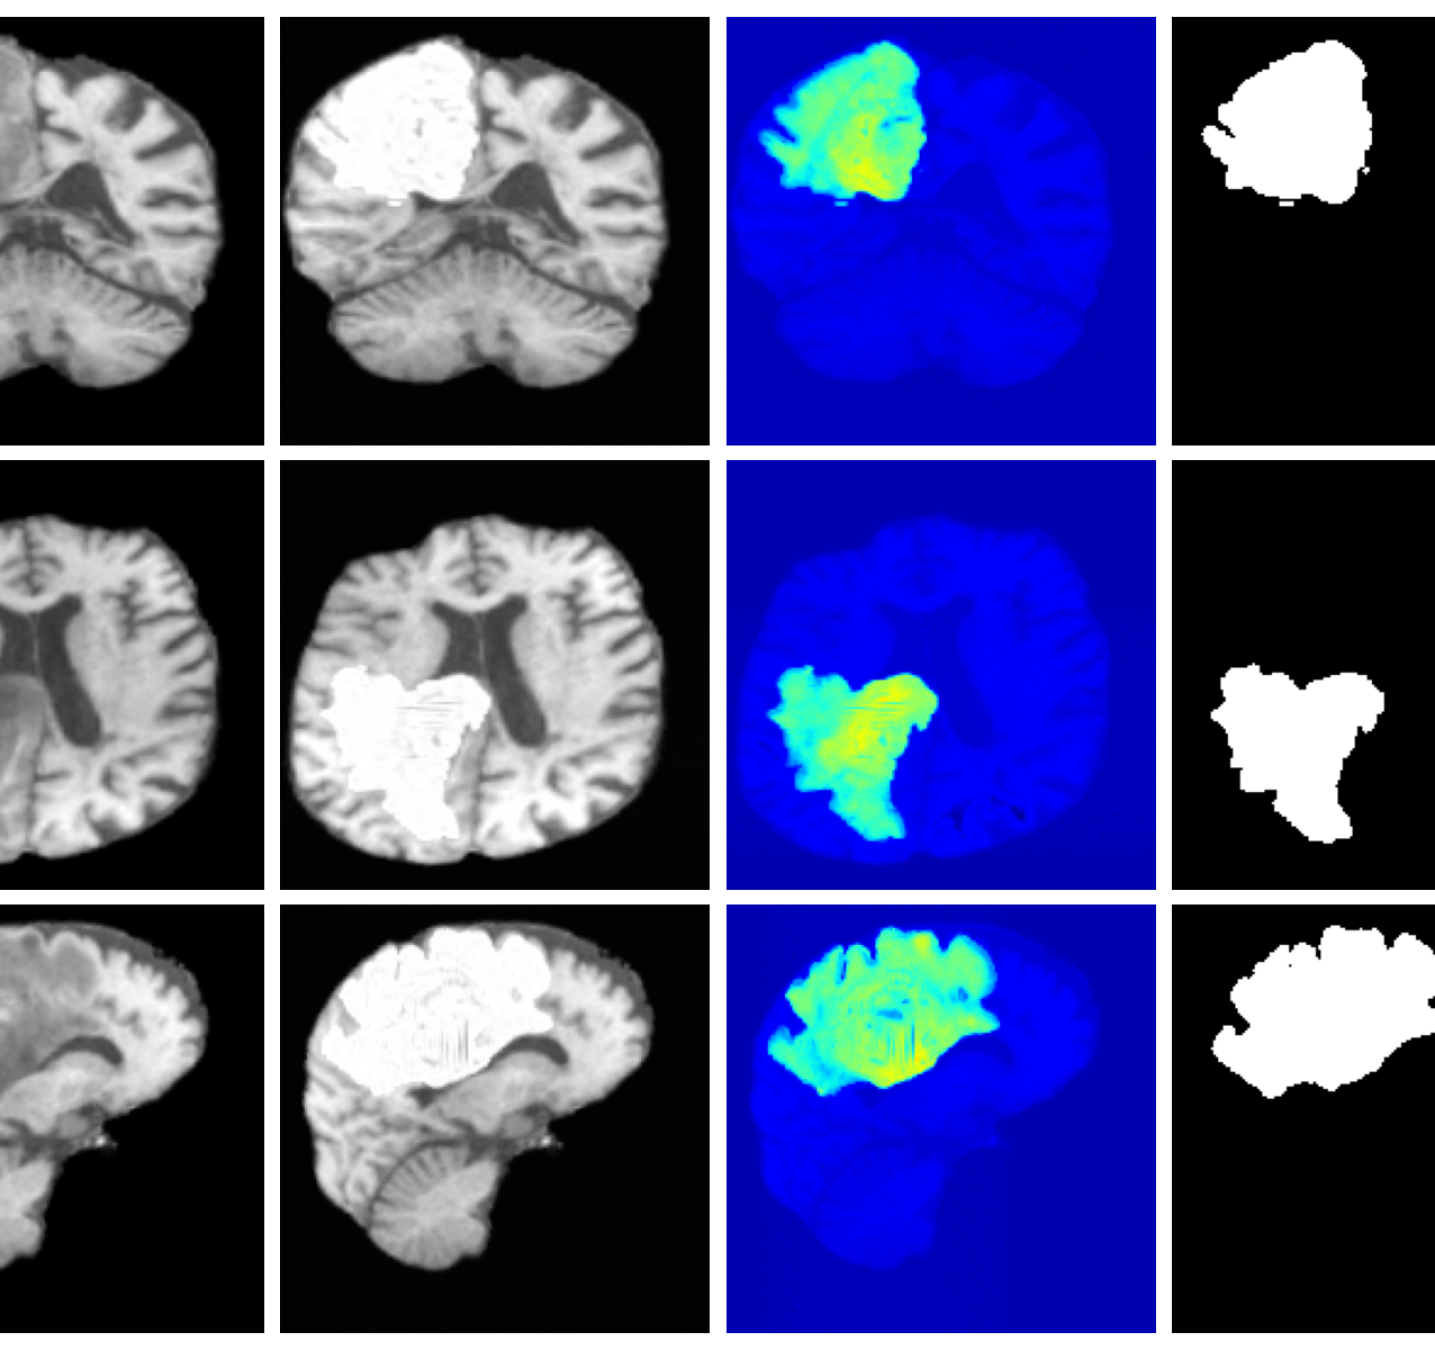

Inpainting. In some cases, we may wish to inpaint disease or corrupt regions of an image with realistic healthy tissue while preserving individual anatomical characteristics. This enables the use of a wide range of existing analysis tools that often fail or produce unreliable results in the presence of pathology. For such inpainting tasks, we can define the likelihood given a binary mask where indicates healthy pixels and indicates pathology pixels and defining a selection matrix where is the number of healthy pixels:

This formulation allows the prior to determine the values of disease regions while constraining healthy pixels to match the data.

4.3 Image inpainting results

Inpainting results are given in Table 3. Our method achieves the best overall performance, attaining the highest rank on both datasets. For ATLAS, our method outperforms all baselines with improvements of 39.2% (VAE), 8.3% (VAE), 2.7% (VAE), 44.2% (LDM), 19.0% (LDM), and 51.4% (LDM). On BraTS, it improves over the best baselines by 25.6% (VAE), 5.2% (VAE), 27.4% (LDM), and 15.2% (LDM), while remaining competitive on the remaining metrics.

Figure 3 (additional examples in Appendix A.9) shows that SynthSR preserves healthy tissue but struggles with large lesions, while DDPM-2D and DDPM-3D, despite producing high-contrast anomaly maps, generate unrealistic homogeneous inpainting, consistent with their lower performance in Table 3. In contrast, our method yields the most anatomically plausible inpainted regions, although anomaly maps appear subtle due to low contrast between lesions and healthy tissue.